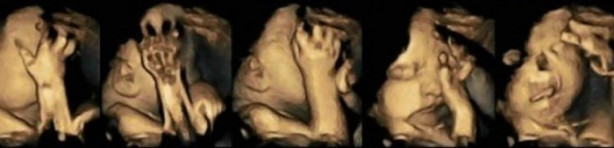

Yapılan çalışmalara göre, 4D ultrason cihazıyla sigara içen annenin karnındaki bebeğin tepkileri görüntülendi.

Çalışmalara 24- 36 haftalık hamile 20 denek anne adayı katıldı.

20 denek annelerin 4’ü günde 14 sigara kullanırken, 16’sı hiç kullanmıyordu. Bu denekler 3 ay boyunca 4 boyutlu ultrason cihazıyla görüntülendi.

Çıkan sonuç ise hayret ettirdi. Sigara kullanan annelerin fetüsleri ultrasonda aşırı stresli ve rahatsız gözüktü. Acı çekermiş gibi bir yüz ifadesi olan bu bebeklerin ağız hareketleri de oldukça fazlaydı.

Doktorlar bu durumu sigara kullanan annelerinin bebeklerinin merkezi sinir sisteminin gelişmemesine bağladı.

Sigara kullanmayan annelerin bebekleri ise ultrasonda daha sağlıklı ve huzurlu görünüyorlardı.